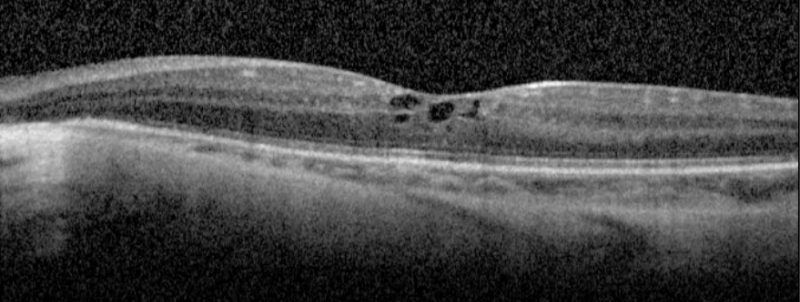

SD-OCT in a patient with gyrate atrophy demonstrating foveal cystoid macula edema. Photo courtesy of Dr. Marc Mathias, MD

| current | 09:18, April 9, 2019 | 1,758 × 663 (650 KB) | Eric.Weldy (talk | contribs) | SD-OCT in a patient with gyrate atrophy demonstrating subfoveal cystoid macula edema. Photo courtesy of Dr. Marc Mathias, MD |